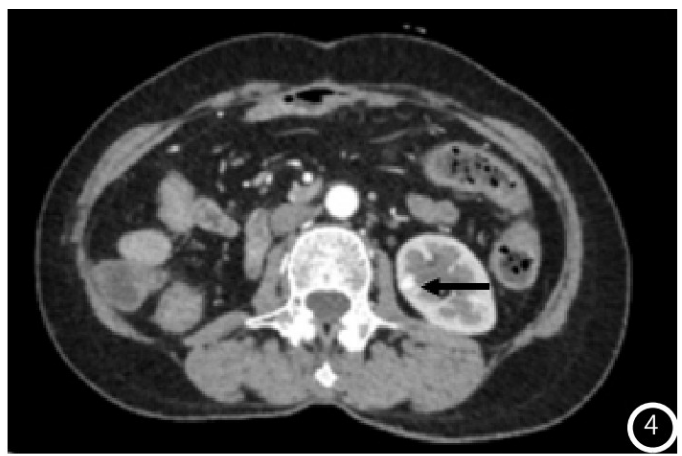

示胰头类圆形低密度结节,大小约14mm×12mm,增强扫描动脉期结节明显均匀强化(图1),强化程度高于正常胰腺实质,静脉期强化减低,边界清;术后4年常规胸腹部CT

图4 CT增强皮质期左肾明显强化结节影(黑箭头);